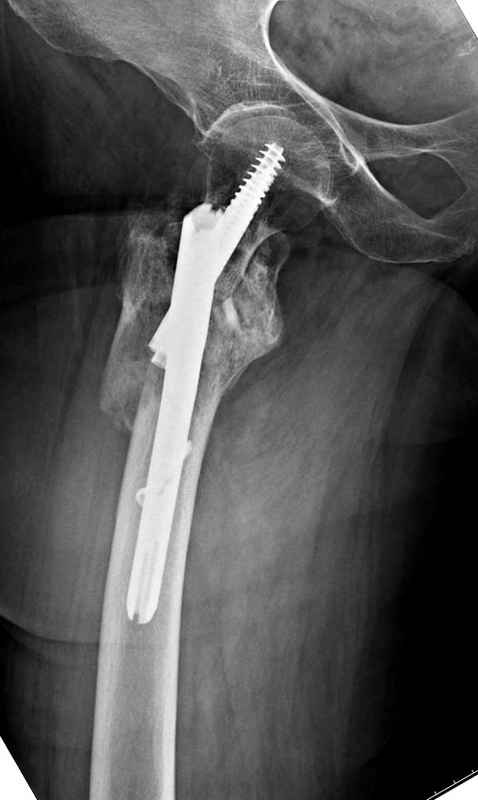

Здесь пара случаев фиксации похожих переломов:

первый высокоэнергетическая травма 36 лет

Djoldas Kuldjanov, M.D.

Department of Orthopedic Surgery

St. Louis University